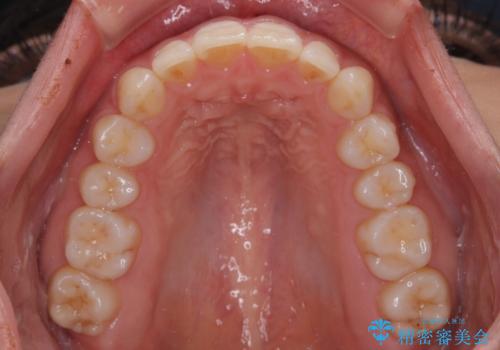

【モニター】突出した前歯 補助装置を併用したインビザライン矯正

- 上下前歯が非接触となり、前方に突出していることを気にして来院された患者様です。

咬合力が強く、全体的に歯がすり減っているため、インビザライン単独での上顎歯列移動は困難と判断し、補助装置により上顎歯列を後方移動させ、その後インビザラインにて仕上げていくこととしました。

補助装置なしでも改善できる可能性はありましたが、補助装置で確実性を上げ、短期間できっちりと仕上げることができました。